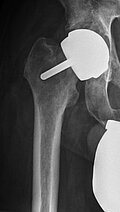

Periprothetischer Hüftgelenksinfekt bei einliegender Hüft TEP

Kurze Vorgeschichte: Herr B., 56 Jahre, hatte Anfang des Jahres 2017 einen Oberflächenersatz des Femurkopfes rechtsseitig (McMinn Prothese, Abb. 1) implantiert bekommen. Mit Schmerzen in der rechten Hüfte erfolgte im Herbst 2017 erstmalig die Vorstellung in domo.

Patientenbezogene Angaben: Der Patient war bei der primären Vorstellung in einem gutem AZ und EZ (181cm, 84 kg Körpergewicht). Er berichtet an rezidivierenden Pneumonien zu leiden. Zuletzt habe er im Februar 2017 eine Pneumonie (nicht näher beschrieben) erlitten. Anschließend habe er eine Lungenarterienembolie entwickelt. Diese habe er jedoch schon einmal 2002 gehabt. Weiterhin sei er kardiologisch mit einer hypertrophen, obstruktiven Kardiomyopathie vorerkrankt. Weiterhin habe er vor 30 Jahren eine Splenektomie erhalten. Genauere Angaben hierzu hat er nicht gemacht.

Verlauf: Im Juli 2017 habe er auf Grund von anhaltenden Schmerzen im Bereich des rechten Kniegelenkes eine diagnostische Arthroskopie erhalten. Genauere Befunde liegen uns hierzu nicht vor. Im weiteren Verlauf seien Schmerzen im Bereich der rechten Hüfte hinzugekommen, weshalb eine erste Vorstellung in unserer Notaufnahme erfolgt.

Vorstellung in der Notaufnahme: Nach der klinischen Untersuchung des Patienten wurde ein Aufnahmelabor durchgeführt (Leukozyten 8.900 Leukozyten/ µl, CRP 79,5 mg/l). Die weiteren Laborparameter zeigten sich, bis auf eine Anämie (Hb 9,5 g/dl) unauffällig.

Eine Röntgenaufnahme des Beckens sowie der rechten Hüfte wurde durchgeführt. Hier wurde der Verdacht auf eine Implantatlockerung gestellt und ein CT der rechten Hüfte veranlasst. Hierbei zeigte sich neben den Lockerungszeichen im Bereich der Pfanne und des Implantates im Femur ein Verhalt zwischen Gluteus medius und maximus. Die Hüfte rechtsseitig wurde punktiert und ein multisensibler E. coli festgestellt. Es erfolgte die Planung zur stationären Aufnahme und Revision der rechten Hüfte.

Procedere: Nach der entsprechenden Vorbereitung erfolgte im September der Ausbau der McMinn-Prothese sowie die Resektion des Schenkelhalses, ein Débridement im Bereich des Hüftgelenkes sowie die Einlage eines Spacers (i.S. einer Copal Zementeinlage) in die Hüftpfanne und im Bereich des proximalen Femurschaftes (Girdlestone Situation). Ende November 2017 erfolgte 6 Wochen nach Spacer Implantation (Abbildung 2) eine erneute Wiedervorstellung zur Punktion des Hüftgelenkes als Vorbereitung auf den Prothesenwiedereinbau. Hierbei wurde erneut ein E. coli detektiert und eine antibiogrammgerechte Antibiose mittels Ciprofloxacin 500mg 1-0-1 fortgesetzte. Die Indikation zum Spacerwechsel wurde gestellt. Der Eingriff konnte geplant Anfang Dezember durchgeführt werden.